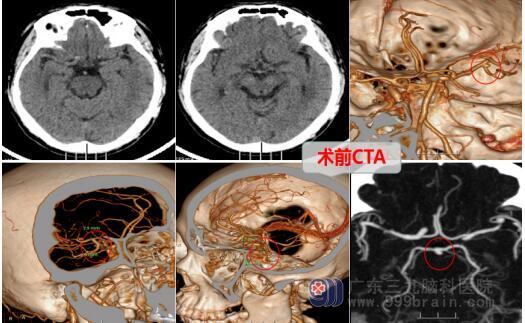

年过半百的李先生几天前出现头痛、头晕,到当地医院就诊,查出患有左侧大脑中动脉瘤M1段动脉瘤。由于医疗条件有限,当地医院的医生建议李先生到上级医院就诊。

神经外十科团队为其制定了紧急开颅手术,显微镜下夹闭动脉瘤的手术治疗方案。动脉瘤夹闭术是经过开颅并找到动脉瘤所在的载瘤血管,使用特殊的动脉瘤夹子将动脉瘤颈进行夹闭,从而阻断它的血流,动脉瘤便不会因为血流冲击而破裂了,同时动脉瘤所在的血管的供血还要不受影响,从而达到治愈的目的。

李先生果断的接受了医疗团队的手术方案,并在完善术前准备后,由欧阳辉教授为首的神经外十科团队为患者行左侧后交通动脉破裂动脉瘤夹闭术。经过几个小时的奋战,成功地完成了手术。术后的李先生精神良好,进入了下一阶段的治疗。